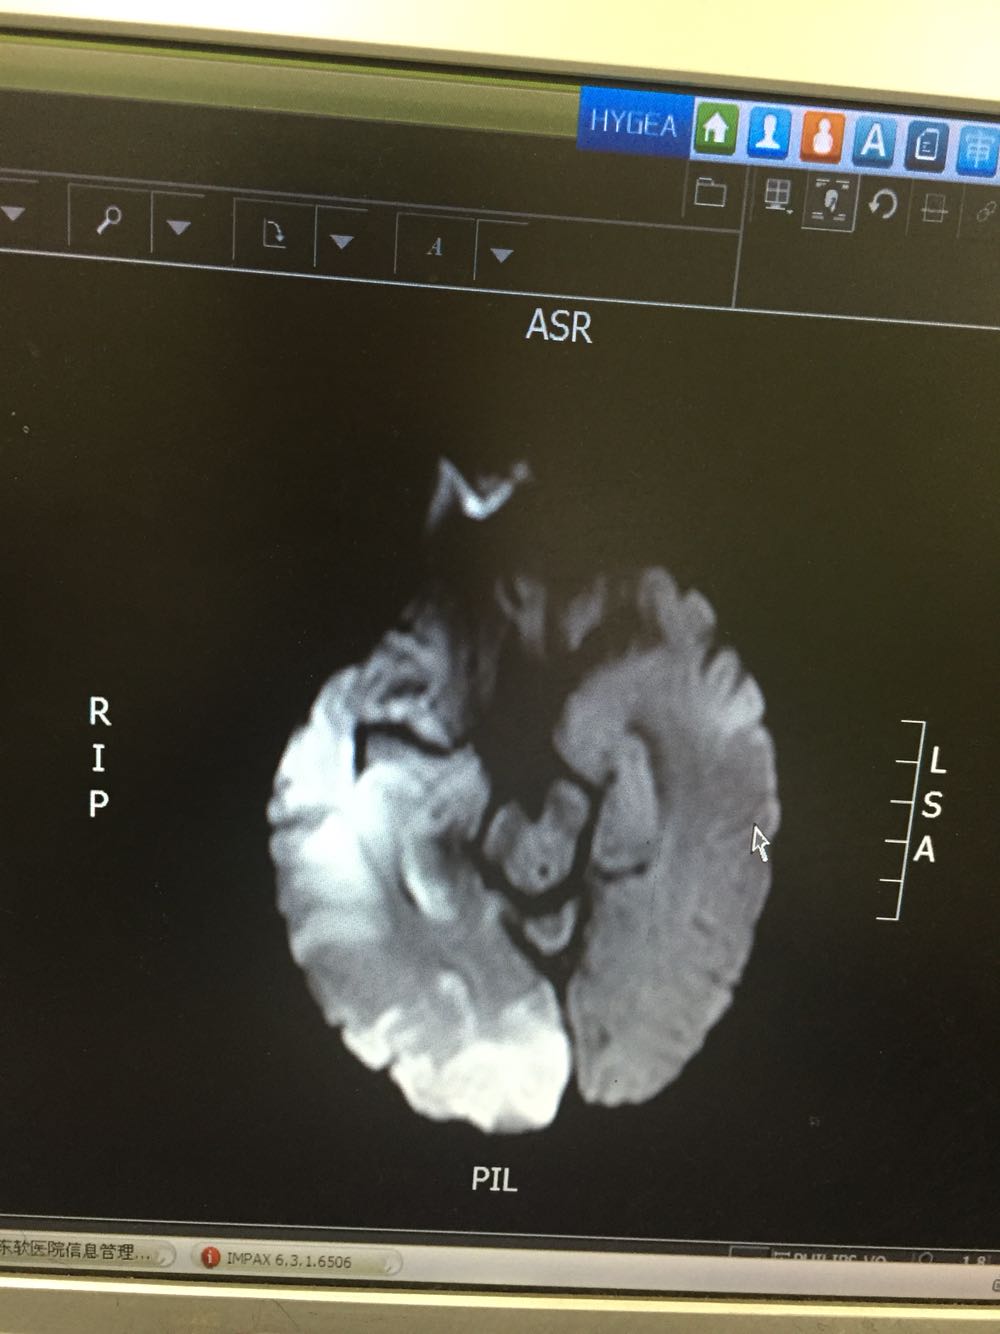

患者入院治疗后症状一度好转,左侧肢体肌力3级+,于入院后第二日病情突然加重,伴意识障碍,头DWI示:脑梗死伴脑出血 右侧大脑中动脉闭塞。停止当前治疗方案,脱水脑保护,营养神经对症治疗。入院后第5日复查头CT示:右侧大面积脑梗死,脑出血吸收期,伴左侧枕叶脑出血。患者左侧枕叶脑出血不好解释,能否是搬运及护理时外伤所致?